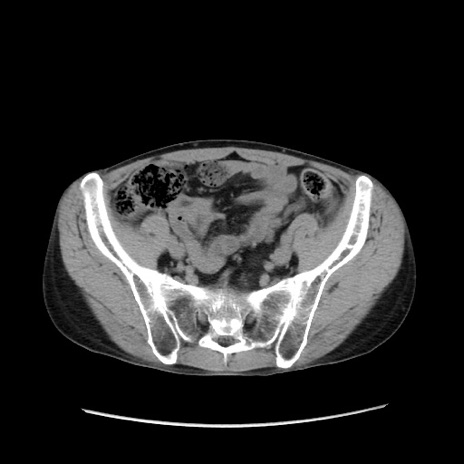

冠状断像

症例37(横断像)

【症例】40歳代 男性

【主訴】腹痛

【現病歴】4時間ほど前に電車に乗車中に臍部上より腹痛出現。徐々に増悪し起立困難となり、救急外来受診。生ものは数日食べていない。今朝お雑煮を食べた。

【身体所見】BT 36.8℃、BP 117/84mmHg、HR 91/min、SpO2 97%、苦悶様、腹部:臍上部広範囲圧痛あり、反跳痛±

【データ】WBC 8100、CRP 0.03